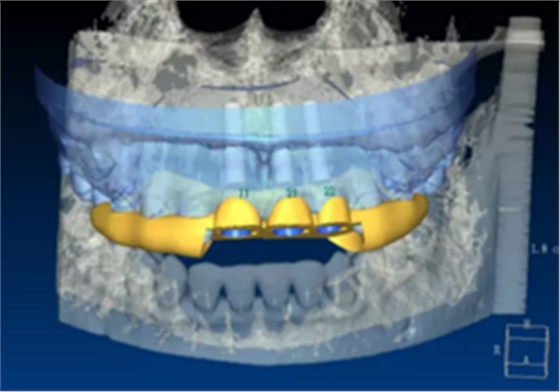

(1)术前准备。拍摄临床照片、拍摄轻开口位CBCT(NewTom)、取聚醚印模灌制超硬石膏模型。 构建数字化模型并设计修复体:将超硬石膏模型在口外扫描(Identica? Hybrid),获取软硬组织表面形态,构建数字化模型,确认咬合情况。根据 天然牙残根颈部形态设计修复体颈部形态,使修复体颈缘轮廓与原有天然牙 一致;按正常牙弓弧度与覆 、覆盖关系,结合红白美学等原则确定修复体 的三维形态。最后,导入患者面部照片,确认模拟修复效果。 设计种植体位置并制作多级导板:利用Segma设计软件,将CBCT数据 和模型扫描数据进行配准,调入模拟修复效果数据,以修复为导向设计种植 方案,设计种植体螺丝孔开口从修复体舌窝处穿出,最终实现螺丝固位的一 体化基台冠修复。根据种植体信息设计多级导板,参考修复体形态设计导板 植入区颈缘外形,打印生成种植导板(Segma),并安装金属引导环。 设计并制作临时修复体:如前所述,按照美学效果和咬合关系设计临 时冠外形,颈部形态与模型龈缘轮廓一致,保证临时修复体在术后可以封闭 拔牙窝。3颗临时冠为连冠,龈外展隙适当加大,为术后软组织生长提供一 定的空间。在临时冠近两侧邻牙的切角处预留翼板,保证临时冠戴入时可以 找到准确的位置。以铣削的方式加工临时冠(Segma),待种植体植入后 将其在口内粘接于临时基台上。

图5 设计种植体位置与多级导板